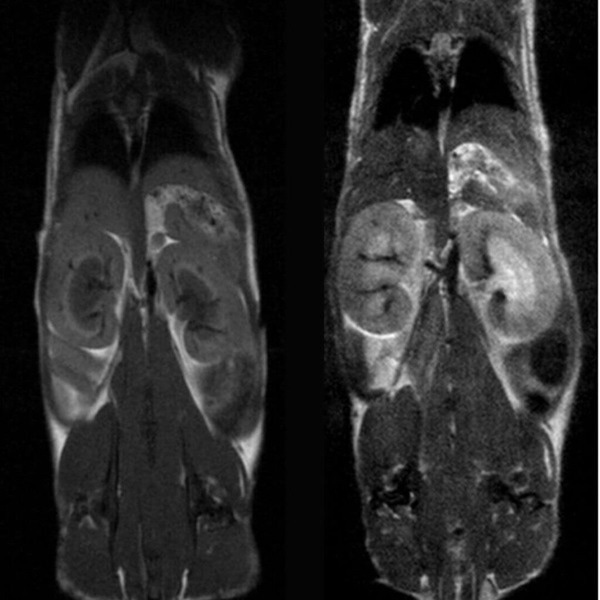

Hindlimb tumor growth: Monitoring the growth of xenograft tumor grown in the mouse hindlimb is identified with T2-weighted images. Segmentation of tumor region of interests (in red) on each tumor-containing slice allows accurate volume quantification. Image Credit: Scintica Instrumentation Inc

Monitoring the growth of xenograft tumor grown in the mouse hindlimb is identified with T2-weighted images. Segmentation of tumor region of interests (in red) on each tumor-containing slice allows accurate volume quantification. Image Credit: Scintica Instrumentation Inc